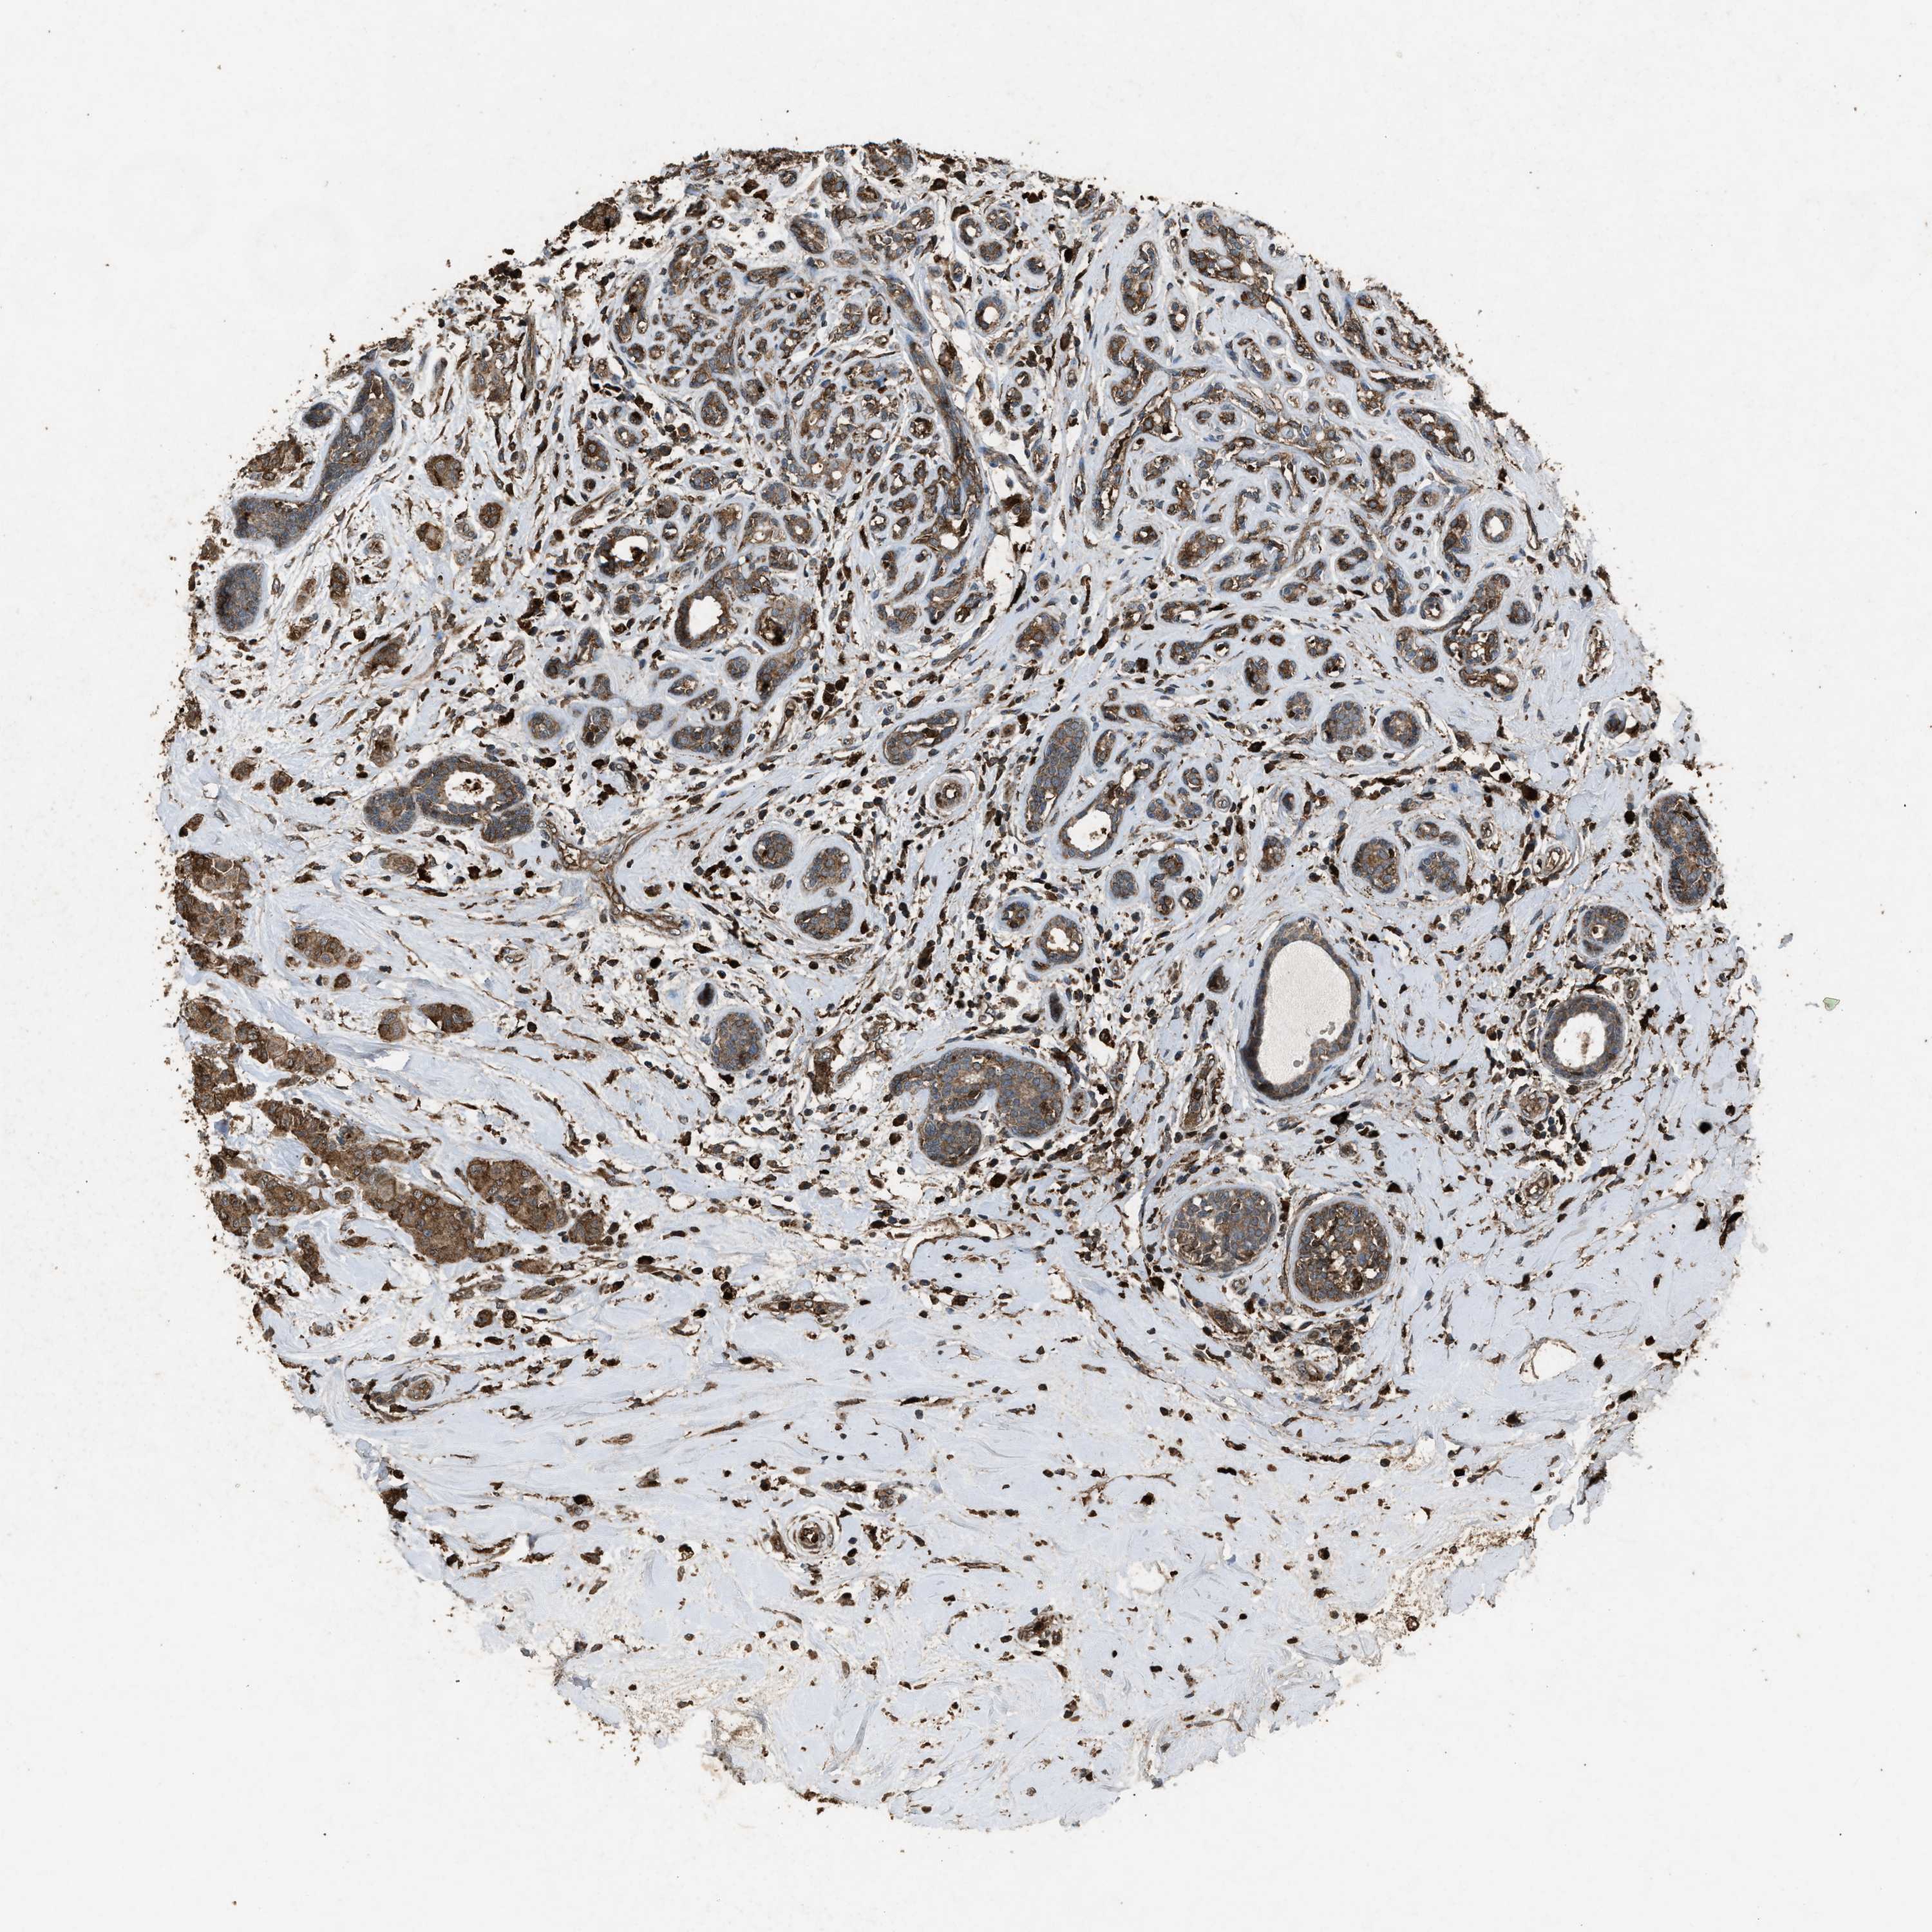

BRCA TCGA BRCA VALIDATION PROTEIN EXPRESSION

ANTIBODIES

AND

VALIDATION